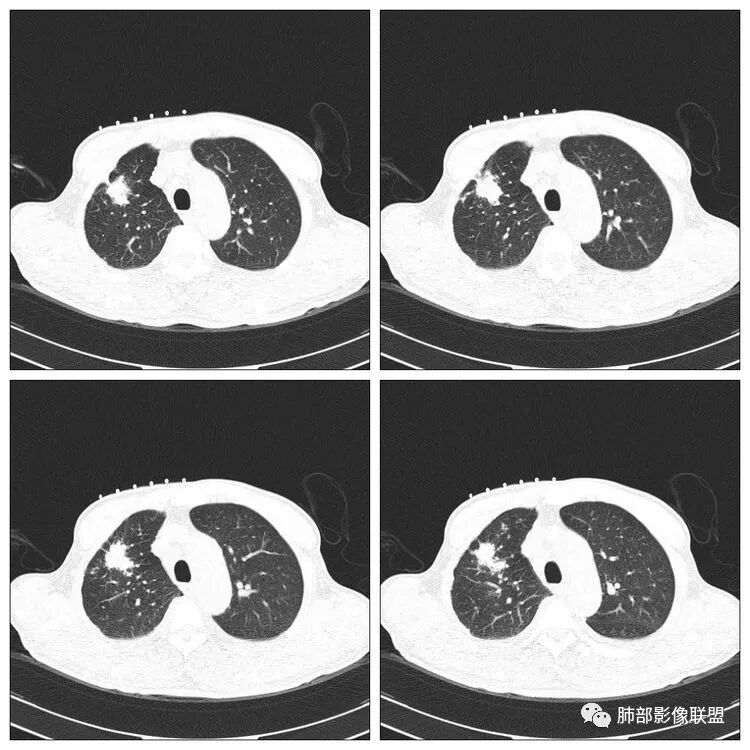

右侧胸廓稍塌陷,右肺体积稍变小,右肺上叶结节,有膨隆有收缩,局部膨隆明显,见胸膜牵拉,胸膜多发增厚,周围卫星灶,另两肺感觉多发微结节影,应该是有结核的,右肺上叶大结节需警惕合并肺腺癌,建议完善增强和三维重建,另两肺多发微结节,有贲门癌病史,需除外转移瘤。

老年男性,有肿瘤病史,右肺上叶肿块,病灶多发毛刺,胸膜牵拉,边缘考虑月牙铲,病灶见空泡征,病灶体积偏大,有恶性征象我首先考虑肿瘤,鉴别结核。

没意见:老年男性,贲门癌病史;CT:右肺上叶前段块状影,病灶由上至下纵轴跨度略长,轴位多个层面提示分叶、膨隆,毛刺,局部平直、内收、凹陷;病灶略散,主体病灶周边卫星灶,支气管树芽征,胸膜增厚,牵拉凹陷,4R淋巴结稍大;整体感觉良恶征象皆有,遗憾没有增强,无法进一步确认,目前转移瘤可能性小,考虑结核可能性较大,需要与原发肺癌鉴别;

老年男性,贲门癌病史。胸CT:右侧胸廓塌陷,右肺体积变小,右肺上叶大结节,深分叶、胸膜牵拉、毛刺,周围卫星灶,两肺多发微结节影,纵隔多发肿大淋巴结,先考虑恶性,结核待排。

水晶石头:患者老年男性,术前胸部CT发现。胸部CT:右肺上叶不规则结节影,可见分叶、毛刺、胸膜凹陷、平直征象,周边可疑卫星灶。综合考虑良性病灶,结核可能性大,结合其明确诊断贲门癌,鉴别转移及恶性。

浪迹天涯:老年男性,贲门癌病史,右肺上叶病灶,局部有深分叶,边缘清楚,周围可见多发点状高密度影,邻近胸膜增厚(其脂肪层可见,未被侵犯),1.结核可能性大,2.腺癌合并结核。

王秀仙:右肺上叶肿块,边缘有平直收缩,部分边缘膨隆,有分叶,有毛刺,周围见较多卫星灶结节,邻近胸膜反应增厚牵拉;考虑结核。

右肺上叶肿块影,边界清晰,其内密度均匀,病灶边缘见分叶,毛刺及胸膜牵拉征,病灶周围见结节及卫星灶,结合病史,考虑腺癌可能,除外转移。

红日东升:老年男性,贲门癌病史。右肺尖段病灶,收缩明显,多发毛刺,胸膜牵拉,局部胸膜增厚牵拉,周围卫星灶,右上叶体积较小。考虑炎性肉芽肿,结核可能,鉴别腺癌。

蔡磊:右肺上叶结节,边缘较清,边缘有收缩,临近胸膜局限性增厚,周围见散在卫星灶,支气管未见明确截断,病灶内密度基本均匀,纵隔内多发增大淋巴结,总体考虑结核,建议增强后再观察,虽然有胃癌病史,转移瘤不是太像。

曹志勇:病灶分叶,局部欠彭隆,胸膜牵拉明显,但周围有卫星灶,首先考虑结核,鉴别腺癌,转移瘤基本不考虑。

马宁强:右肺上叶肿块,边缘有平直收缩,部分边缘膨隆,有分叶,有毛刺,周围见较多卫星灶结节,邻近胸膜反应增厚牵拉;考虑结核。

弹指之间:右上肺结节,毛刺、分叶,局部胸膜增厚牵拉、凹陷,恶性征象比较多,但周围卫星灶,纵隔淋巴结增大,第一考虑结核可能,腺癌待排吧

但是呢,我觉得这个病灶,它确实有一些恶性的特点,边缘膨隆,深分叶,有深短毛刺。

2.右肺上叶斑片影、结节影、硬树丫,密度均匀未见钙化或液化。近胸壁处见分叶结节影及棘状突起,胸膜牵拉凹陷。

3.近胸壁处边缘分叶结节影,胸膜凹陷等使人怀疑基础疾病上出现新生物的可能性。

4.细看病灶有些散,有堆砌感。注意结核灶也常有胸膜牵拉。